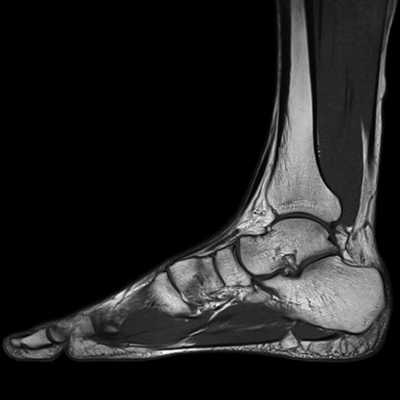

МРТ голеностопного сустава является приоритетным методом диагностики повреждений сухожилий, связок и мышц . Поэтому при переломе лодыжки, сопряженном с суставными травмами, следует сделать магнитно-резонансную томографию.

Что покажет магнитно-резонансная томографияпри переломе лодыжки

МРТ голеностопа использует сильное магнитное поле для создания очень подробных изображений связок, которые помогают удерживать лодыжку вместе.

Что показывает МРТ голеностопного сустава

Поэтому МРТ широко используют в ортопедии и травматологии, онкологии. Вот, что показывает МРТ голеностопа:

Травматические повреждения голеностопа, щиколотки, пальцев стопы.

Состояние после травм голеностопа, чтобы выявить наличие и характер поражения связок (растяжение, разрыв), мышц (ушибы, размозжение, некроз), сухожилий, сосудов (кровоизлияния в мягкие ткани), костей, суставов (вывихи, подвывихи, внутрисуставные переломы). Перелом обычно хорошо виден на рентгенограмме, но сопутствующие повреждения окружающих тканей видны только на МРТ.